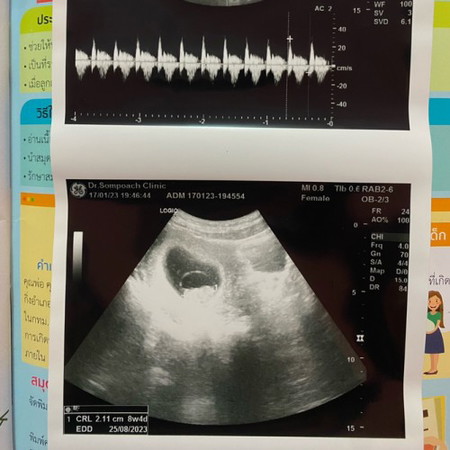

อายุครรภ์ 8w4d

อายุครรภ์ 8w4d ขนาด2.11 cm. น้องตัวเล็กไปมั้ยคะ แม่ไม่ค่อยได้บำรุงเลย ช่วงนี้แพ้ท้องหนักมาก กินอะไรก็อ้วกออกหมด 😂 #ขอคำแนะนำหน่อยค่ะ #ขอบคุณสำหรับคำตอบค่ะ

น่าจะปกติดีค่ะ 8วีคประมาณ 1.6 cm ค่ะแม่ ของแม่ได้ 8w4d แล้วก็เกินมานิดหน่อย น้องยังครรภ์อ่อน ๆ ค่ะ ถ้าหมอไม่ว่าอะไรก็ปกติดีจ้า 💗 ของเราช่วงแรกเบื่ออาหารมาก แต่ก็พยายามกิน แต่โชคดีที่ไม่อ้วกเลย 🥹

น้องตัวใหญ่กว่าของเรามากเลยค่ะ ซาวตอน8.3week 1.45cm เองค่ะ ทั้งๆที่ไม่แพ้เลยค่ะ กินได้ทุกอย่างปกติ

น้องตัวใหญ่น้า ของเรา9w3d 2.17เองค่ะ😅

ของเราตอนไปซาวด์8w3dน้องได้2.26cmค่ะ